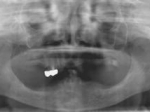

術前レントゲン